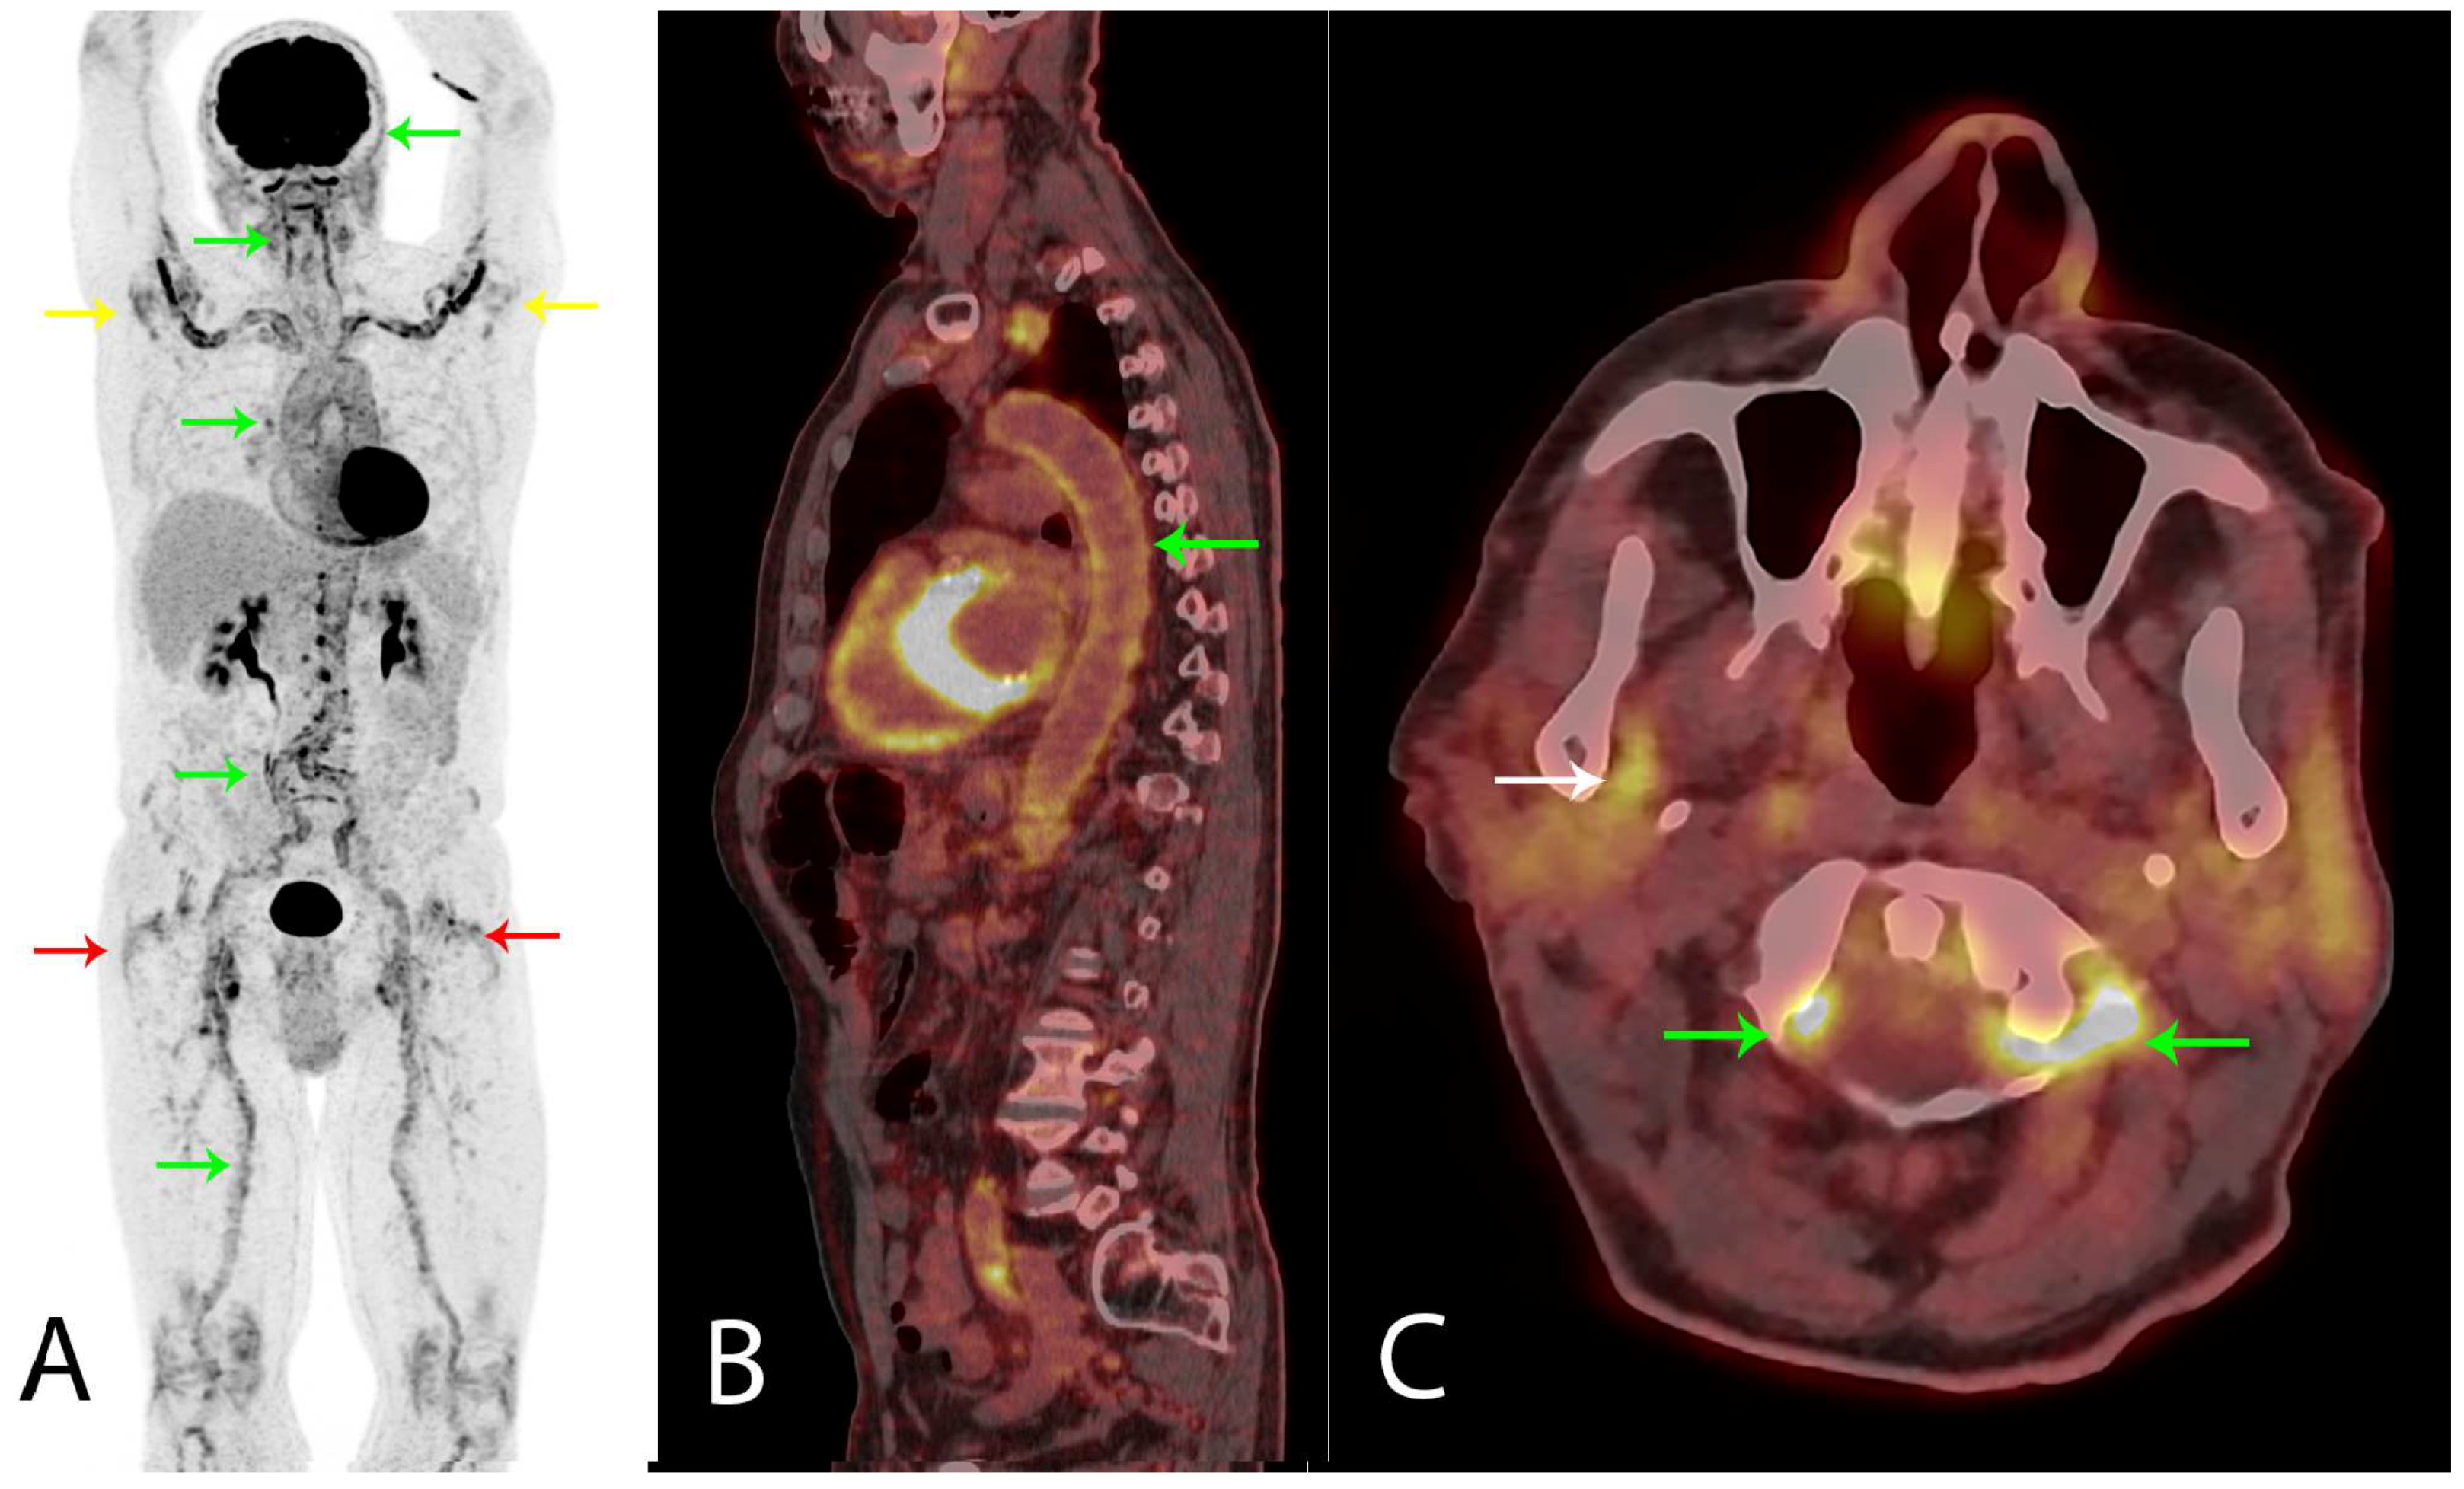

A healthy 80-year old man had, during the last six month period, experienced a 5 kg non-intended weight loss, malaise, coughing, and extreme fatigue. Before the symptoms started, he was physically active and bicycled 20–40 km and rowed 10–15 km per week. As symptoms progressed, muscle tenderness in the shoulder and hip regions made exercising impossible. No morning stiffness of the joints was experienced. Blood tests showed a mild normocytic normochromic anemia, elevated C-reactive protein (100 mg/L), and erythrocyte sedimentation rate (88 mm/h). PMR was suspected, but malignancy was a differential diagnosis. A total of 3.85 MBq/kg 18F-FDG was administrated an hour before a whole body PET/CT scan was performed. (A) Frontal PET MIP showed highly increased 18F-FDG uptake diffusely around shoulder (yellow arrows) and hip joints (red arrows), indicating bursitis, but also in the wall of the large arteries (green arrows), indicating synchronic LVV confirmed on (B) sagittal fused PET/CT of the aorta (green arrow). The LVV aorta and its major branches are affected, but the vertebral (green arrows) and maxillary (white arrow, right side shown) arteries could also be involved, (C) axial fused PET/CT. Notably, the 18F-FDG uptake in the affected arteries (not quantitatively shown) was more than two times the uptake in the liver, which has been shown to accurately indicate LVV on PET/CT [1,2,3,4].